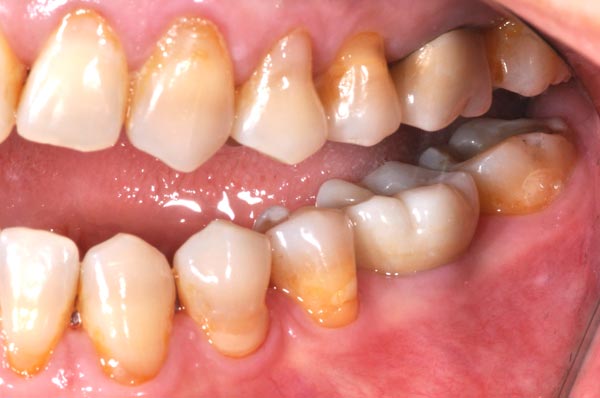

植牙前

植牙後

更多植牙案例

美觀區植牙通常是用於前牙的區域,對於美學較有要求的部位。相較於一般植牙,美觀區植牙更須要注重牙齒美學的考量。另外前牙區的骨壁較薄,缺牙後會有較多的骨質流失,頰側的骨頭容易凹陷。也因此前牙植牙是較具挑戰性的,植牙前各方面的謹慎評估會比一般後牙區植牙來得複雜許多